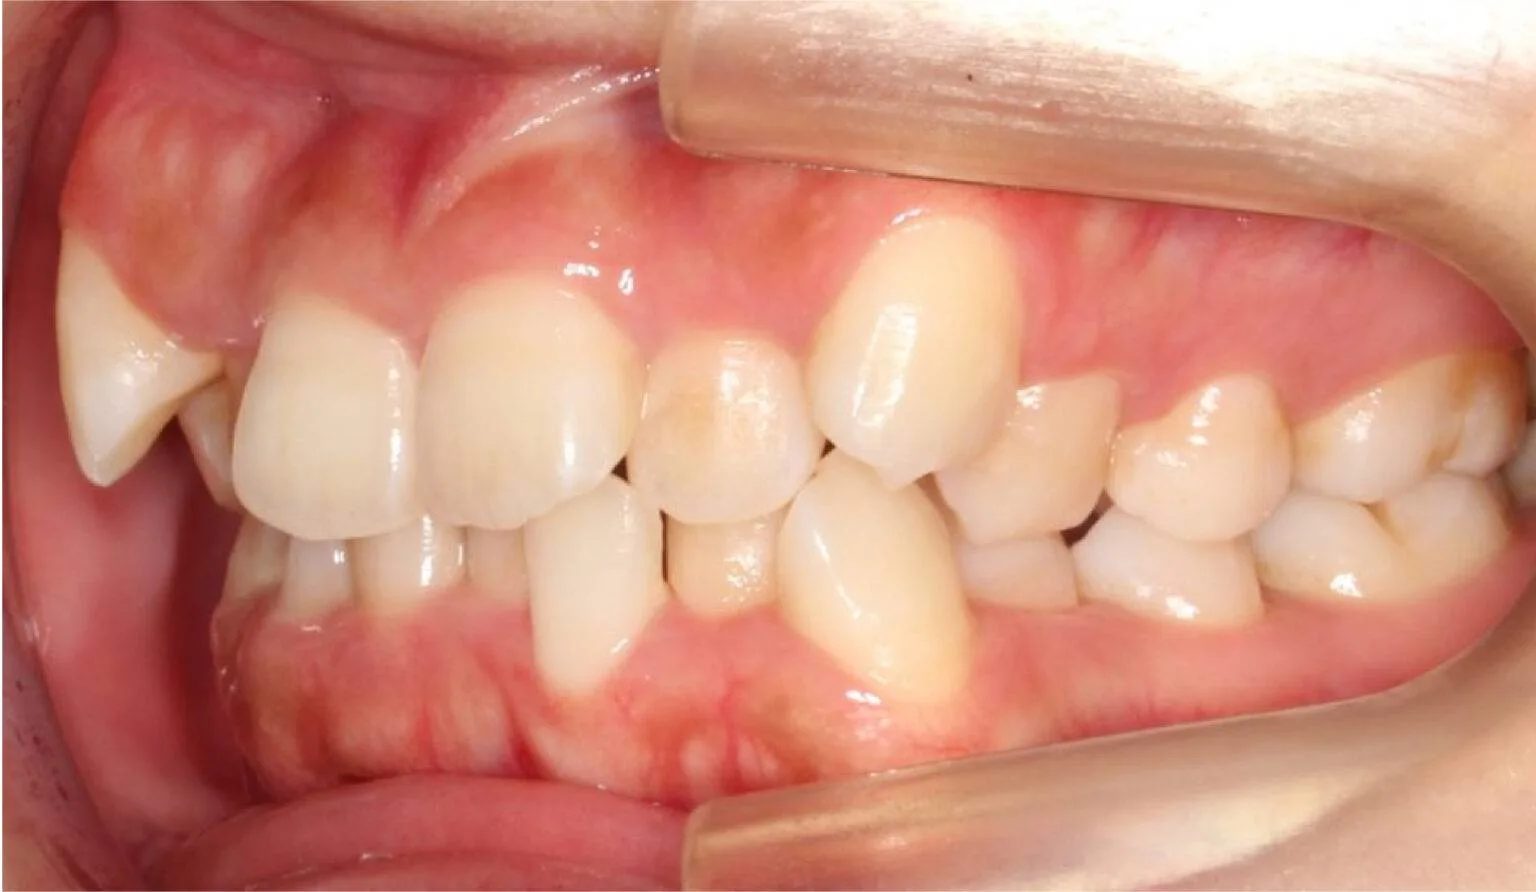

This is where the upper teeth horizontally protrude past the bottom teeth, also called an ‘Overbite’. A common dental complaint we hear that relates to protrusion is ‘my front teeth are sticking out’.

The protrusion of teeth can cause speech problems and make it difficult to consume food, this is due to the fact it can prevent correct biting and chewing.

Protrusion is a dental condition that is usually caused by skeletal issues with the lower jaw, mainly in those who have a growth deficiency. Overbites can cause irreparable soft tissue damage and also contribute to early tooth loss from excessive wear of the teeth. Besides overjets having functional side effects, they can also affect the aesthetics of the smile. Overall, it can look unpleasant to the eye, this can affect a person’s psychological and emotional state.

Protruded teeth commonly come in conjunction with patients with narrow arches, habits of tongue thrusting, swallowing and breathing improperly, phonetic problems – such as enunciating certain words and sounds like F and V, and allergies.

Before overbite treatment showing upper teeth protrusion at SmileBox Dental Clinic After overbite treatment showing corrected bite and balanced smile at SmileBox Clinic